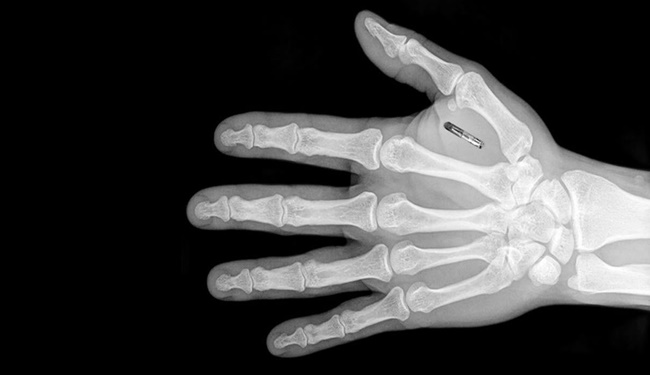

2 mm’ye 12 mm’lik standart bir şırınga ile deri altına enjekte edilebilen mikroçiplerin boyutu ise 1.5 mm’ye 8 mm’yi aşmıyor. Ayrıca 800 byte ile 1 kilobyte arası bilgiyi de bu mikroçipler saklayabiliyor. Bilgiyi saklayabilen mikroçiplerden biri Vulchek’in kartviziti olarak iş görürken diğeri ise bilgisayarına erişmesini sağlayan şifreyi barındırıyor. Bir kripto-anarşist olarak mikroçiplerin elektronik verileri deşifre edebilmesini ve tıbbı amaçlı kullanılabilmesini umut ettiğini belirten Vulchek, şu an bir şeker ölçer mikro çip üzerine araştırmalarının devam ettiğini ve bunun gibi mikroçiplerin bir çok sorunu çözebileceğini ifade etti.

Fakat Vulchek’in bu noktada durmaya niyeti yok. Yakın bir gelecekte bir şifre çözücü, bir tane de şeker ölçer mikroçipi yerleştirmeyi düşünen çılgın doktorun, derisinin altına yerleştiğirdiği mikroçiplerin günlük aktivitelerine yardımcı olan araçlar olarak kullandığı belirtildi. Ellerini sallayarak kapıları açan, mikroçip okuyuculara yaklaştırarak faturalarını ödeyen doktorun hayatının adeta sihir yapan bir büyücü gibi geçtiğini düşünüyoruz. Vulchek’in derisinin altındaki mikroçiplerin işlevleri ise sırayla şöyle:

- Ofisine girmek için yerleştirilmiş iki çip

- Bir taşıt çipi

- Bir kilobaytlık veri saklayabilen iki hafıza çipi

- Sibiryadaki kayak oteli için giriş kartı bilgilerinin olduğu bir çip